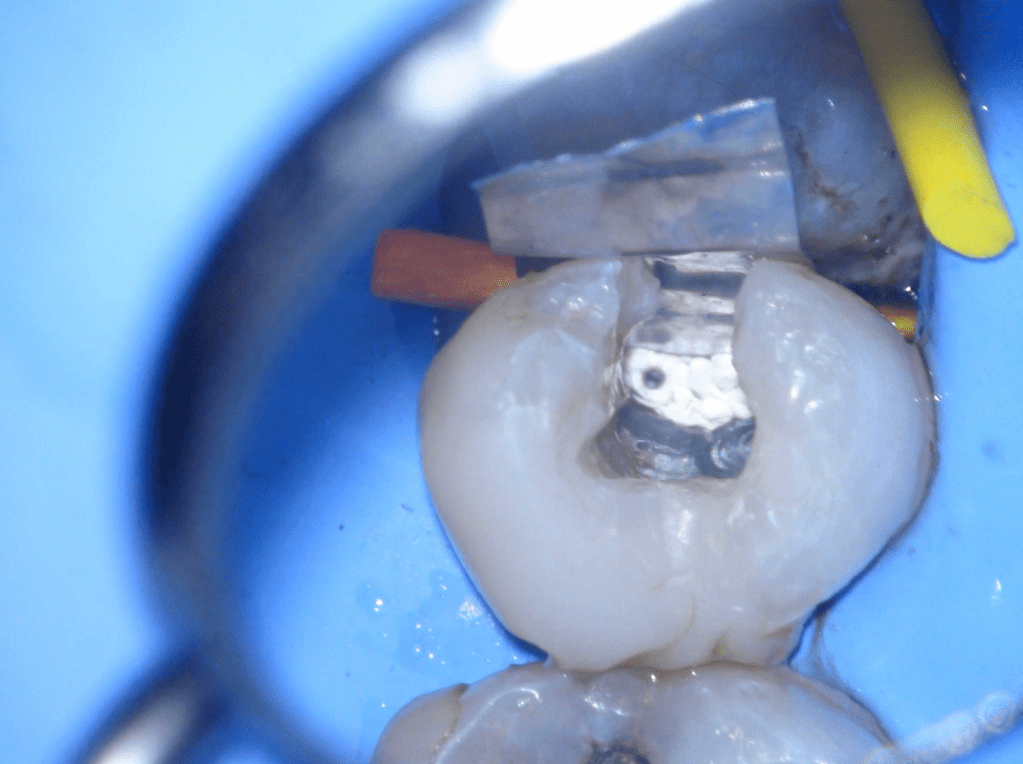

Reconstrucción preendodóntica

Reco preendo + 4 conductos molar superior